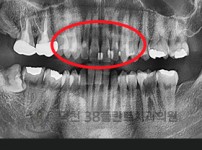

치료전후